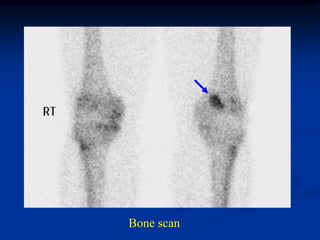

Bone scan

Case #550

59 year female